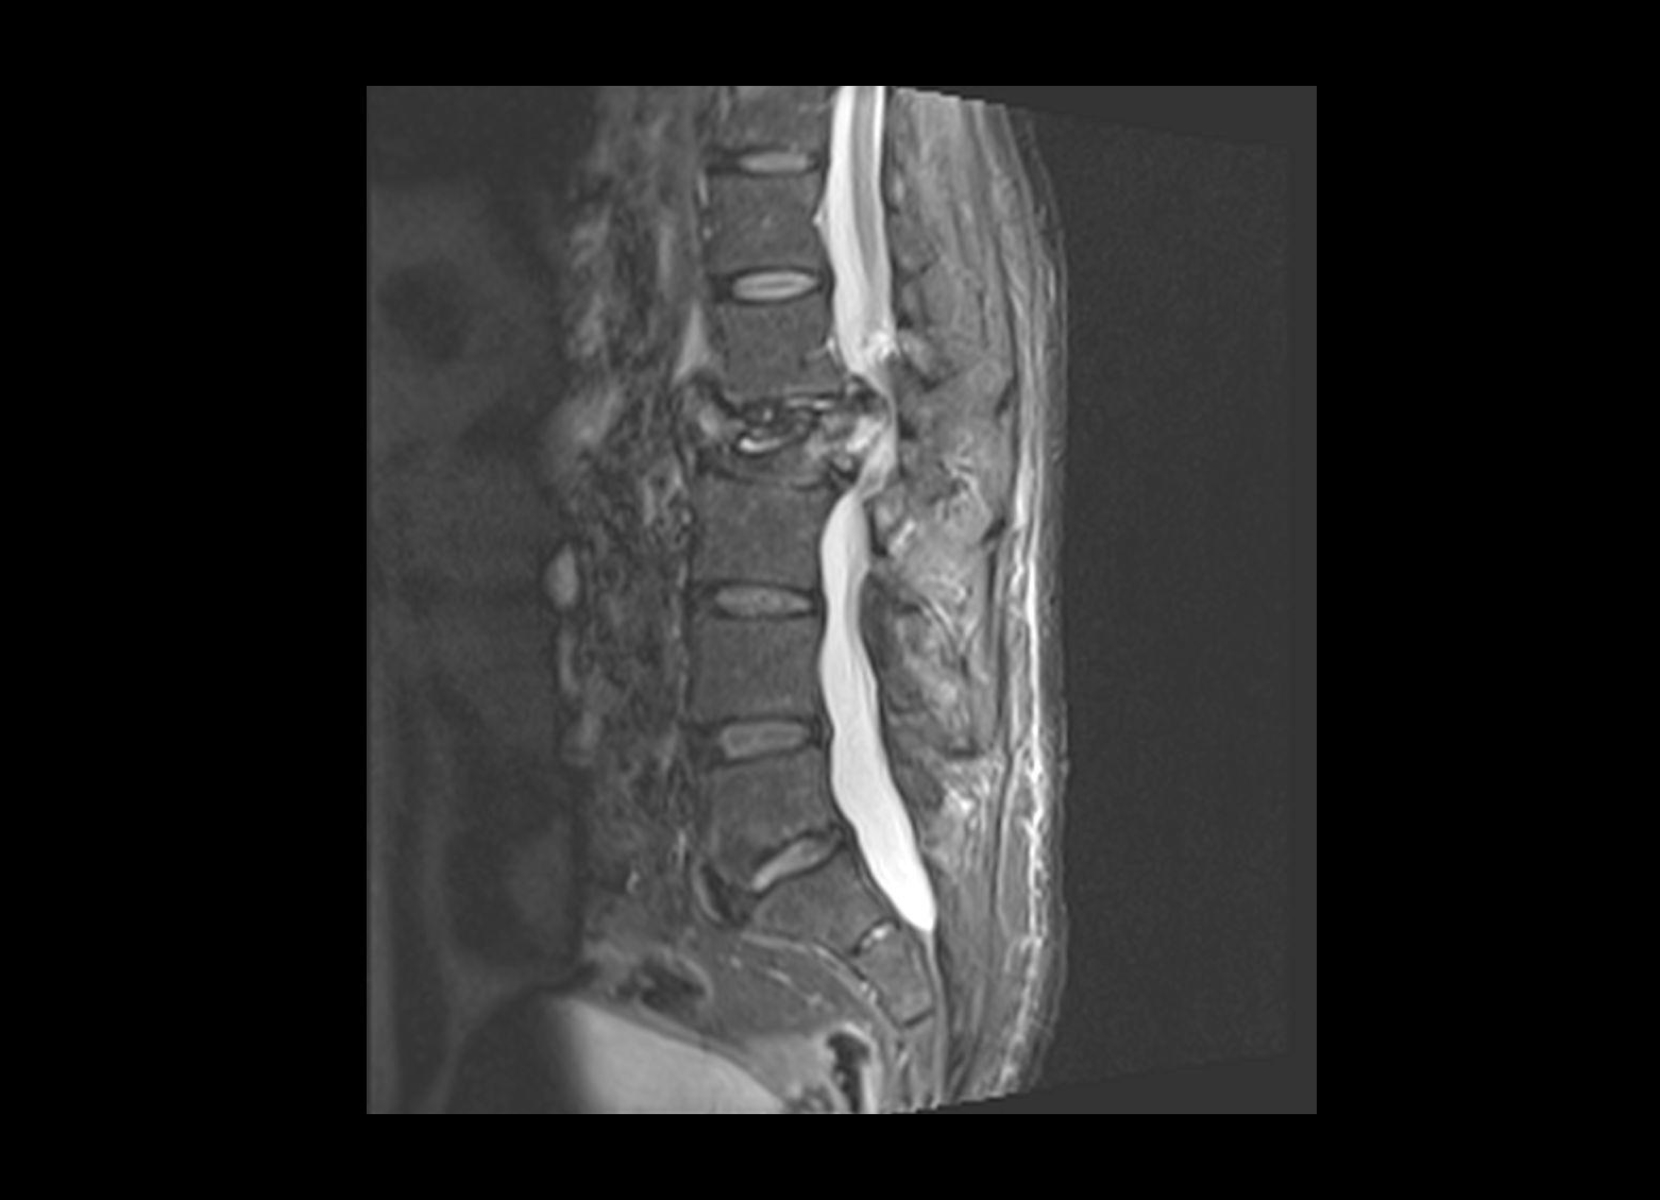

Conventional

STIR

SubtleSYNTH™

(Synthesized STIR)™

Trauma

GE 1.5T

C-spine